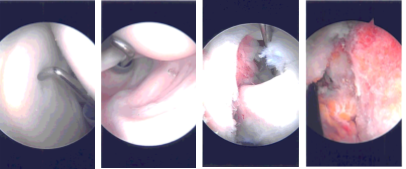

The anterosuperior entry portal was made with a spinal needle under arthroscopic supervision. Incision was given and examination of the cuff was space. with a spur. Probe was inserted from the anterosuperior portal. Glenoid as well as humerus as well as the scapula. The rotator Pictures were taken.

Trocar was inserted through the subscapularis and bursectomy was performed. Examination showed acromial roughening Examination of the rotator cuff showed high-grade partial-thickness tear in the anterior margin of the supraspinatus as well as in the rotator interval. The subscapularis was intact.

The decision was made to close the rotator cuff interval with the suture. The spinal needle was used to pass the PDS suture laterally and FirstPass was used to pass the suture medially. The arthroscope was entered into the glenohumeral joint to pass the suture superficial to the biceps tendon.

Once the suture was checked that it was not around the biceps tendon, the rotator cuff interval and the supraspinatus tear were closed with sliding knots. Acromioplasty was performed with the use of Coblation wand followed by burr.

Distal clavicle excision was also performed given the arthritis present. Coblation wand followed by burr was used to excise about a centimeter of the distal clavicle. The final pictures were taken and saved.

Intraoperative Arthroscopy Images